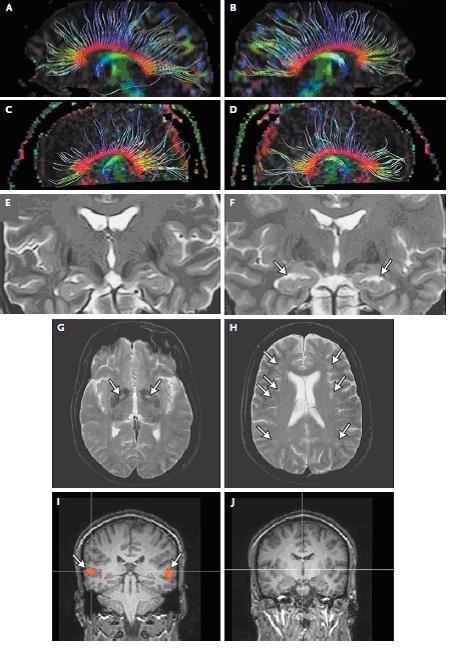

La risonanza magnetica (RM) cerebrale pu� rilevare reperti alterati dopo un avvelenamento da CO (Figura 3). Sono state descritte lesioni dei gangli della base e atrofia dell�ippocampo o di altre strutture anni dopo l�avvelenamento; nessuna di queste lesioni � specifica per� dell�avvelenamento da CO.

Figura 3. Reperti della risonanza magnetica dopo avvelenamento da monossido di carbonio

Nelle figure viene mostrato il danno cerebrale da monossido di carbonio, osservato nei pazienti avvelenati con sequele. Le immagini sono state ottenute con l�uso di un apparecchio 3-T MR altamente sensibile, non disponibile ovunque, secondo protocolli specifici; nel quadro A e B sono mostrate le strie delle fibre della sostanza bianca di un volontario sano di 22 anni, mentre nel quadro C e D sono mostrate le fibre della sostanza bianca di un soggetto della stessa et� con una storia di avvelenamento da CO. I quadri E e F mostrano rispettivamente le immagini coronariche dell�ippocampo di un volontario sano e di un paziente dopo l'avvelenamento da CO. In un paziente � stata trovata (quadro F, frecce) atrofia dell�ippocampo, lesioni del globus pallido (quadro G, frecce) e delle strutture sottocorticali (quadro H, frecce). Il risultato della funzione auditiva alla RM dopo l' avvelenamento da CO in un paziente con una precedente acutezza auditiva normale, mostra una normale attivazione dopo stimolazione auditiva all�orecchio destro (quadro I, frecce) e nessuna attivazione della funziona auditiva a sinistra (quadro J). Questo reperto � caratteristico di un processo auditivo, normale da un lato (destro in questo caso) e soppresso dal lato opposto, presumibilmente in relazione con la lesione cerebrale da avvelenamento da ossido di carbonio.